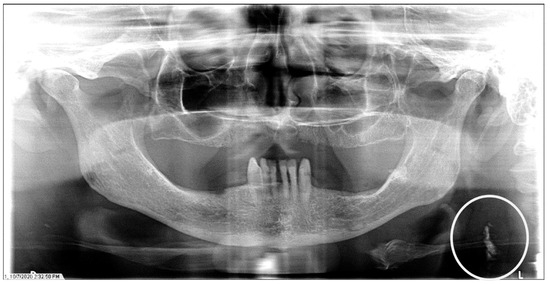

The characteristics of the CAC patients are presented in Table 1. Between 2014 and 2023, there were 559 patient records with the terms “carotid artery calcification” or “carotid” or “calcification of the carotid artery” noted. After the panoramic radiographs were reviewed, 314 patients were confirmed to have a diagnosis of CAC (including 26 patients with a history of carotid endarterectomy). The remaining 245 patient records were excluded because of the absence of detectable CAC on PRs and the absence of PRs to review. The ages ranged from 29 to 92 years, with a median of 68 years. CAC was most prevalent (39.5%) in the seventh decade of life. There were 168 (53.5%) female and 146 (46.5%) male patients. The median age of the female patients was 68 years, and the median age of the male patients was 69.5 years. The calcifications were identified unilaterally in 168 (53.5%) patients (88 females/80 males; mean age: 67.8 years) (Figure 1 and Figure 2) and bilaterally in 146 (46.5%) patients (80 females/66 males; mean age: 68.6 years) (Figure 3, Figure 4 and Figure 5). The DMFT index in the CAC patients ranged from 8 to 32 (mean = 26.6). The frequency of patients with CAC with a history of hypertension, hyperlipidemia, diabetes mellitus, CVA, and CAD was 86.2%, 57.6%, 30.7%, 15.5%, and 28.7%, respectively.

Figure 1.

The panoramic radiograph of a 67-year-old male patient with a medical history of hypertension, diabetes mellitus, and coronary artery disease showing a unilateral right carotid artery calcification (CAC) during a comprehensive dental examination. The CAC is encircled by a white line.